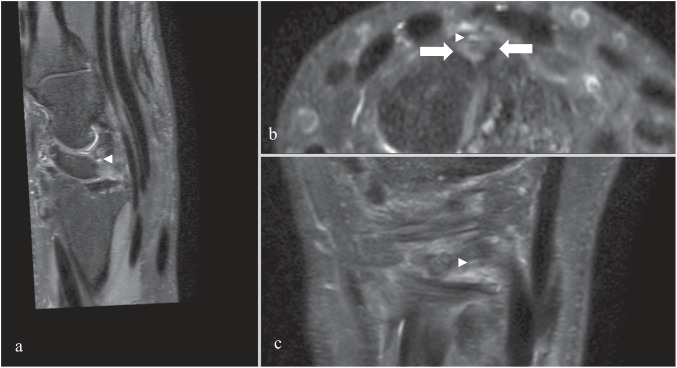

Twenty-eight percent (42/150) of patients had specific SL (scapholunate) dorsal pain, 39 showed injury to the SL ligament (palmar and/or intermediary and always associated with a partial or complete dorsal lesion; see Fig. 5), 30 of who were found to have cyst communication with the joint.

Fig. 5.

3D DP SPAIR images in MPR mode with a partial tear of the dorsal SL with a cyst next to the stumps of the ligament. a Sagittal plane; b axial plane; c coronal plane. Arrow = stumps of SL ligament; arrowhead = cyst